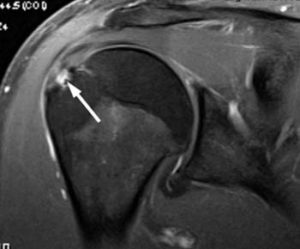

Arthroscopic Subacromial Decompresion is a procedure in which surgical instruments are inserted into two or three small puncture wounds around your Shoulder. Your doctor examines your Shoulder through a fiberoptic scope connected to a television camera. He or she guides the small instruments using a video monitor, and removes bone and soft tissue. In most cases, the front edge of the Acromion is removed along with some of the bursal tissue.

Your surgeon may also treat other conditions present in the Shoulder at the time of surgery. These can include arthritis between the clavicle (collarbone) and the Acromion (Acromioclavicular Arthritis), inflammation of the biceps tendon (biceps tendonitis), or a partial Rotator Cuff Tear.